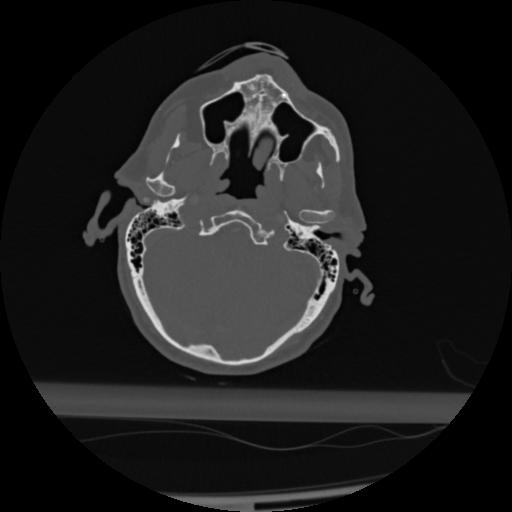

22 ANGIO,CE,Vol,0.5,ANGIO,,